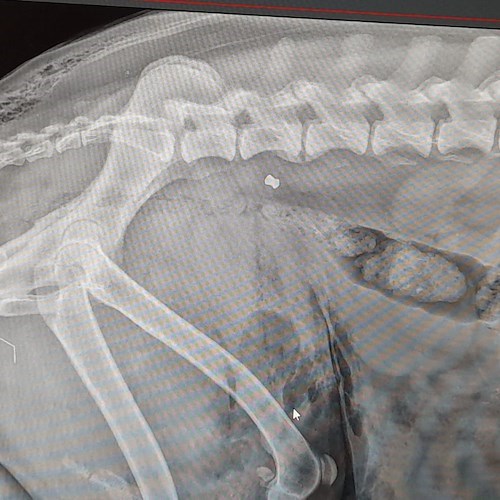

Gli esami clinici hanno purtroppo confermato il sospetto peggiore: Nebbia è stato colpito con un'arma da fuoco. I veterinari hanno riscontrato numerosi pallini da caccia nell'addome, nella schiena e in altre parti del corpo. La zona addominale, in particolare, è interessata da un vasto ematoma interno, complicazione che rende estremamente difficile qualsiasi intervento chirurgico immediato.

Le condizioni restano gravi e riservate, ma il cane sta lottando con tutte le sue forze per sopravvivere.